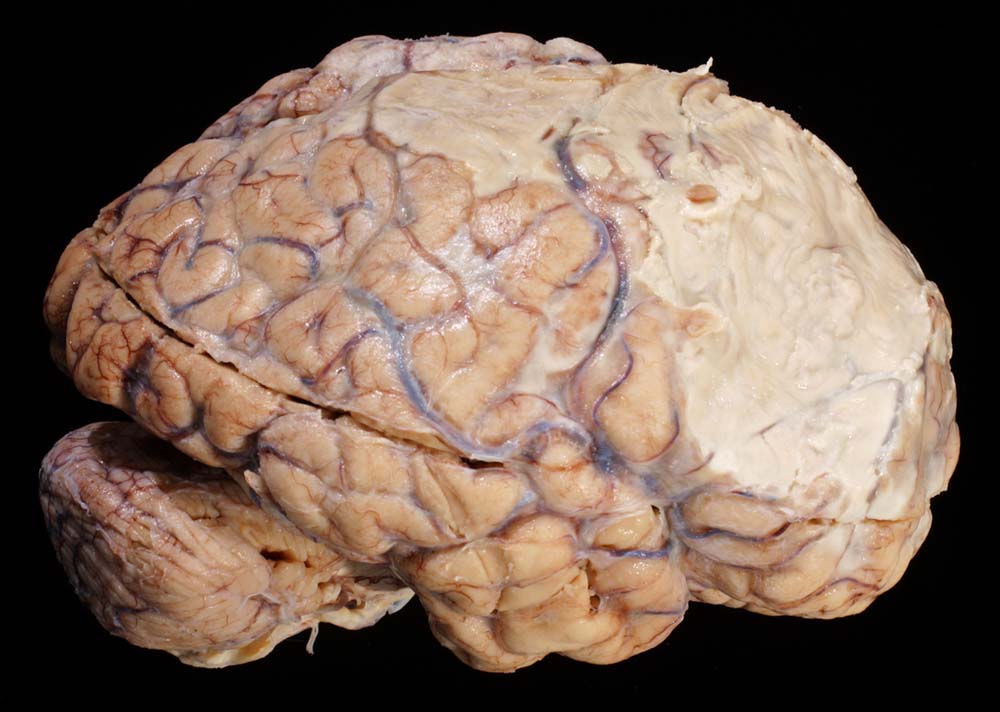

Morphologie:

Der makroskopische Befund bei bakterieller Meningitis kann sehr diskret sein. Die meningealen Gefässe sind hyperämisch und die Hirnoberfläche wird von einem grüngelben Eiterbelag bedeckt (eher basal bei Hämophilus influenzae, eher über der Konvexität bei Pneumokokken=Haubenmeningitis). Histologisch ist der Subarachnoidalraum mit Eiter gefüllt. Bei weniger schweren Fällen finden sich die neutrophilen Granulozyten bevorzugt um die leptomeningealen Gefässe.